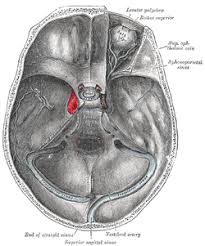

Nasal cavity definition, anatomy, functions, diagrams. General information about paranasal sinus and nasal cavity cancer. Medial wall of nasal cavity (nasal septum). The nasal cavity is divided into two symmetrical halves by the nasal septum, a central partition of bone and cartilage; Gross anatomy the nasal cavity is formed by 1:

Nasal Cavity Paranasal Sinuses Maxillary Division Of Trigeminal from www.wesnorman.com In this article, we shall look at the applied anatomy of the nasal cavity, and some of the relevant clinical syndromes. This cavity is a space that runs along the top of the roof of the mouth (the palate, which separates your nose from your mouth) and then turns downward to join the passage from the mouth to the throat. The nasal cavity is posterior to the nose and is framed and supported by several bones and cartilages. The nasal septum divides the cavity into two cavities, also known as fossae. Nasal cavity and paranasal sinuses. Signs and symptoms of paranasal sinus and nasal cavity cancer include sinus problems and nosebleeds. It consists of nasal skeleton, which houses the nasal cavity. Inferior, middle and superior nasal conchae (turbinates) superiorly:

Nasal nebulization is a more effective method of delivering topical medication than nasal spray. Inferior, middle and superior nasal conchae (turbinates) superiorly: The nasal cavity forms part of the aerodigestive tract. Gross anatomy the nasal cavity is formed by 1: Medial wall of nasal cavity (nasal septum). The nasal cavity is posterior to the nose and is framed and supported by several bones and cartilages. As part of the septum nasi (septum nasi) distinguish membranous. Nasal cavity and sinus tumors are usually treated with surgery. In this article, we shall look at the applied anatomy of the nasal cavity, and some of the relevant clinical syndromes. The nasal cavity is divided into equal halves by the nasal septum and the vomer bone. Each cavity is the continuation of one of the two nostrils. The reserve crowns of the upper cheek teeth and a portion of the paranasal sinus system occupy this area of the skull. Ralph abi hachem, md, msc, c.

In addition to being an integral part of the respiratory system, your nose also serves as the organ of olfaction or smell. It consists of nasal skeleton, which houses the nasal cavity. Signs and symptoms of paranasal sinus and nasal cavity cancer include sinus problems and nosebleeds. Learn vocabulary, terms and more with flashcards, games and other study tools. Use the screens to enhance your understanding of. The goal of the surgery is to remove the whole tumor and a small amount of normal tissue don't take more of any medication than the amount directed on the label or as instructed by your healthcare provider. Abi hachem engages the ent residents at duke university hospital, instructing them on how to dissect the nasal cavity to expose the frontal sinus, and identifying relevant anatomy. This model is shown in the trigeminal three trigeminal nerve network under the internal structure of the oral cavity and throat, according to the head in side. Cribriform plate of the ethmoid. General information about paranasal sinus and nasal cavity cancer. Scott brown, md duke university medical center. Ralph abi hachem, md, msc, c. The cavity of the nose (cavum nasi) is divided by the septum of the nose into the right and left halves.